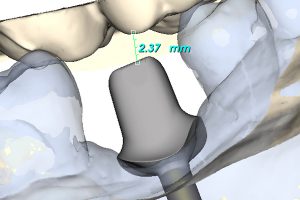

- posiada projektowany indywidulanie optymalnie położony brzeg preparacji tak, że stopień dla posadowienia korony znajduje się minimalnie poddziąsłowo lub dodziąsłowo, co ma istotne znaczenie w profilaktyce zapaleń okołowszczepowych typu cementitis,

Po zamontowaniu tzw. skan lokatorów i zeskanowaniu modelu, wypełniany jest formularz zamówienia na łącznik. Zawiera on wszystkie niezbędne informacje dotyczące sposobu wykonania łącznika zgodnie z życzeniem zamawiającego takie, jak: rodzaj materiału, kompresja tkanek miękkich, profil wyłaniania, angulacja, wysokość okluzyjna, głębokość posadowienia poddziąsłowo stopnia dla korony itp. Następnie formularz ten (tzw. Atlantis WebOrder) łącznie ze skanami przesyłany jest do Centrum Projektowania i Frezowania Atlantis. W odpowiedzi na zamówienie otrzymujemy wirtualny projekt łącznika do akceptacji w programie Atlantis VAD. W zależności od tego, czy projekt spełnia nasze oczekiwania, czy też wymaga zmian, do Centrum Projektowania wysyłana jest określona informacja. Po ostatecznym za- akceptowaniu projektu łącznika, zamówienie otrzymuje status realizacji i łącznik przekazy- wany jest do produkcji. Po kilku dniach łącznik trafia do laboratorium, gdzie jest sprawdzany na modelach gipsowych i odsyłany do kontroli klinicznej.

Mimo, że w większości wypadków łącznik nie wymaga korekt, to zdarza się, że klinicznie korygowane są pewne jego elementy (np. położenie stopnia dla korony). Na kluczu do pozycjonowania przenosi się łącznik i ustawia w platformie protetycznej implantu oraz przykręca w ustalonej pozycji śrubo- krętem dynamometrycznym. Następnie pobierany jest drugi wycisk z indywidualnie przygotowanym transferem wyciskowym na łyżce zamkniętej, tym razem z poziomu łącznika. Takie postępowanie ma wiele zalet: pozwala na uniknięcie błędu pozycjonowania stożka w platformie protetycznej implantu, umożliwia dokładne opracowanie powierzchni stycznych przyszłej korony w stosunku do zębów sąsiadujących oraz dokładnie odwzorowuje stan tkanek miękkich i ich kompresję po przykręceniu łącznika. Następnie, po pobraniu wycisku, do łącznika przykręcany jest drugi analog implantu, łącznik jest osadzany w wycisku i odlewany w laboratorium kolejny model z maska dziąsłową. Tak więc laboratorium ma do dyspozycji 2 modele robocze, które jednak mogą nieznacznie różnić się między sobą. Na drugim modelu przygotowywana jest ostatecznie korona. Łącznik jest skanowany, następnie projektowana jest w systemie CAD/ CAM czapka korony, wycinana z bloczku cyrkonowego, synteryzowana i następnie odsyłana do ceramisty w celu napalenia warstwowo porcelany dentystycznej. Gotowa praca (łącznik i korona) przesyłana jest do kliniki celem ostatecznego osadzenia w jamie ustnej pacjenta podczas kolejnej wizyty.